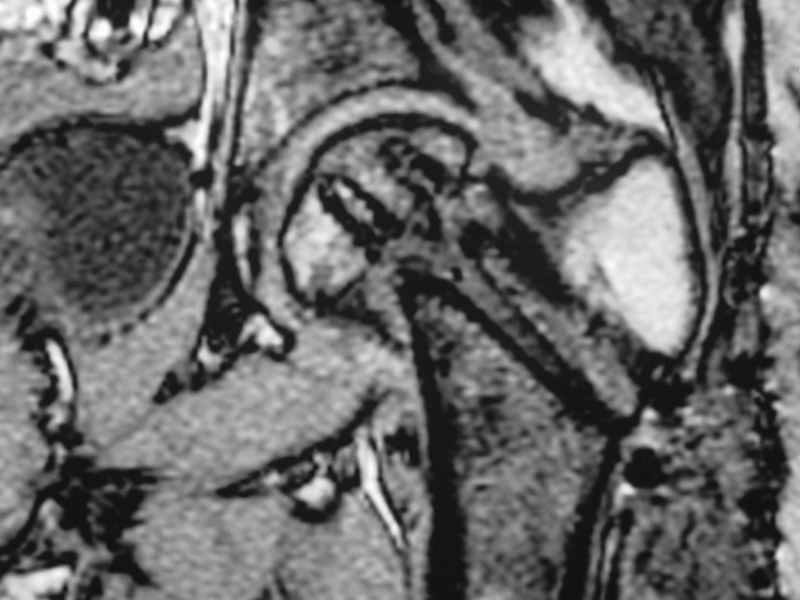

Re: Нелеченный перелом шейки бедра / Neglected fem

dhs will not correct improper biomechanical environment and may further compromise vascular

integrity consider establish vascular status via mri

and if viable follow with proximal valgus osteotomy

case provided s/p failed fixation